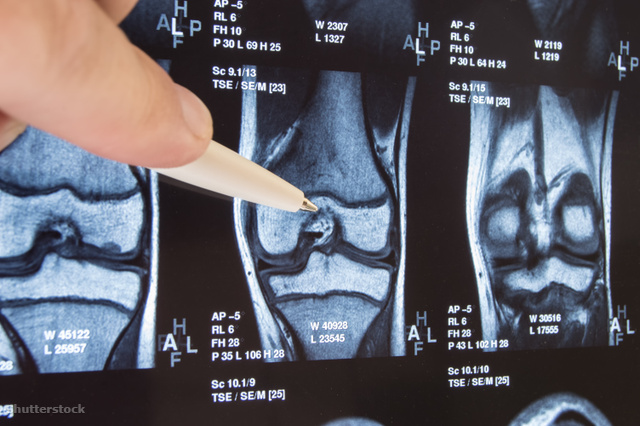

Ízületeknek nevezzük a két csont találkozásánál lévő mozgó részt, mint például váll vagy épp térdízület. Az ízület ennek megfelelően két csontvégből áll, ezt a két csontvéget porc borítja (ha láttunk már csirkecombot, akkor porcot is láttunk). Élő személyben az ízületet körülveszi egy kis zsák, amiben ízületi folyadék van, ez egy csúszós-nyálkás valami, és arra szolgál, hogy a porcfelületek könnyen csússzanak egymáson. Az egészet ízületi szalagok tartják össze.

Ennek megfelelően az ízület működése több dologtól függ. Ha kevés vagy nem megfelelő összetételű az ízületi folyadék, akkor túl nagy a súrlódás a két csontvég között. Még nagyobb a baj, ha a csontvégekről lekopik a porc: ilyenkor mozgáskor két csontvég próbál egymáson elcsúszni-elforogni, de ezek nem csúsznak olyan jól, mint a porc – az eredmény fájdalom és mozgáskorlátozottság. Végső esetben a megoldás a protézis beépítése, ilyenkor az egész cuccot kicserélik fémalkatrészekre. Az ízületi protézis-műtétek nagy műtétek, utána hosszú a gyógyulás, rehabilitáció, szóval jobban tesszük, ha nem jutunk el idáig, hanem inkább igyekszünk megelőzni a bajt.

Gyanús lehet, ha gyakran fájdalmat és ízületi merevséget tapasztalunk tartós pihenés után, majd ezek a tünetek állandósulnak, vagy megváltozik az érintett ízület formája. Ortopéd szakorvoshoz kell fordulni (háziorvos utalhat be), aki valószínűleg röntgenvizsgálatot, ritkábban artroszkópiás vizsgálatot (ízületi tükrözés) javasolhat. Ha kopni kezdett a porc, akkor sem kell pánikba esni, kímélettel, kezelésekkel, mozgásterápiával, gyógytornával lassítható a folyamat.